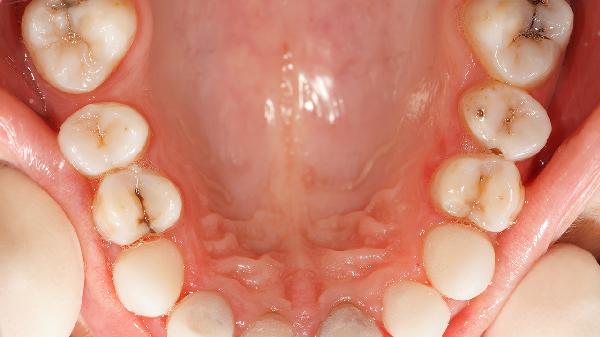

牙齿表面的白色附着物可能是牙菌斑、初期龋齿或牙釉质脱矿的表现。主要有牙菌斑堆积、早期龋齿、氟斑牙、牙釉质发育不全、外源性色素沉积等情况。

牙釉质表层脱矿呈现白垩色斑块,多发生在磨牙窝沟或邻面。此时牙齿尚未形成龋洞,可通过含氟牙膏再矿化治疗。未及时干预可能发展为中龋,出现冷热敏感症状。

牙齿发育期摄入过量氟导致釉质矿化异常,表现为对称性白垩色条纹或斑块。轻症仅影响美观,重症可能伴随釉质缺损。需避免使用含氟量超标的水源,成年后可通过渗透树脂改善外观。

遗传因素或婴幼儿期全身性疾病干扰釉质形成,牙齿表面出现不规则白斑或凹陷。此类牙齿更易发生龋坏,建议每三个月进行涂氟保护,避免进食酸性食物。